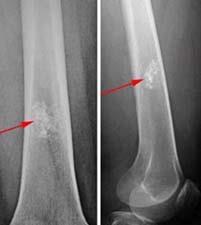

X-rays. X-rays provide images of dense structures such as bone. On X-rays, enchondromas appear as small (less than 5 cm), lobe-shaped, darkened tumors in the middle of the bone. They usually contain white spots or calcification within. The white areas of the tumor show a pattern of rings and arcs that indicates the tumor contains cartilage.

Other imaging tests. Your doctor may order a computerized tomography (CT) or magnetic resonance imaging (MRI) scan to help further evaluate your tumor. These scans give a more complete picture of the bone around the tumor. If the tumor has turned into a malignancy, the scans may show bone erosion, bone inflammation, or a mass growing outside the bone.